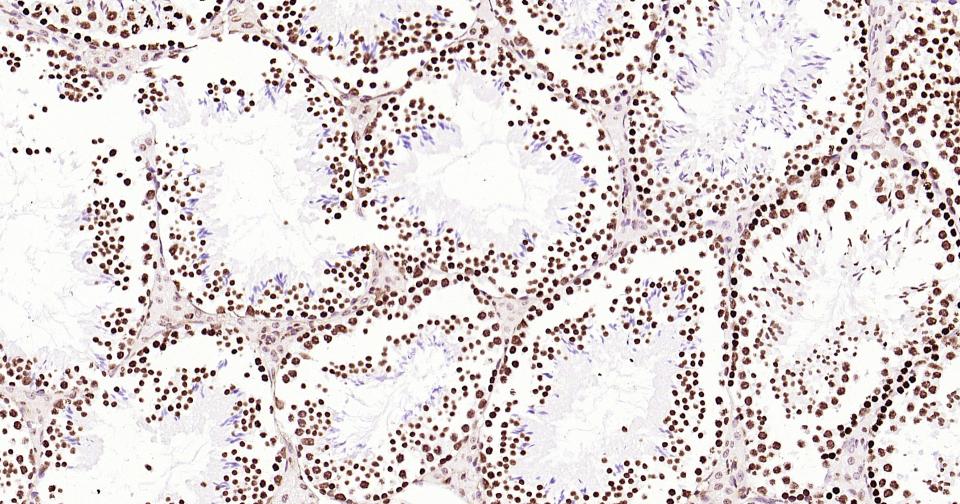

Histone H3 is one of the DNA-binding proteins found in the chromatin of all eukaryotic cells. H3 along with four core histone proteins binds to DNA forming the structure of the nucleosome. Histones play a central role in transcription regulation, DNA repair, DNA replication and chromosomal stability. Post translationally, histones are modified in a variety of ways to either directly change the chromatin structure or allow for the binding of specific transcription factors. The N-terminal tail of histone H3 protrudes from the globular nucleosome core and can undergo several different types of post-translational modification that influence cellular processes. These modifications include the covalent attachment of methyl or acetyl groups to lysine and arginine amino acids and the phosphorylation of serine or threonine.

用吸水纸吸去玻片上多余的液体,加入2-4滴大鼠Histone H3 鼠单抗工作液(试剂5),置于湿盒中,4℃孵育过夜或37℃孵育1-2 h。

*5. 发表论文时引用本产品的写作建议 "IHC0111R, Bioss Antibodies"。引用示例: “Rat tissue sections using Rat Histone H3 IHC Kit (IHC0111R, Bioss Antibodies) were stained for Histone H3 according to the manufacturer's instructions.”